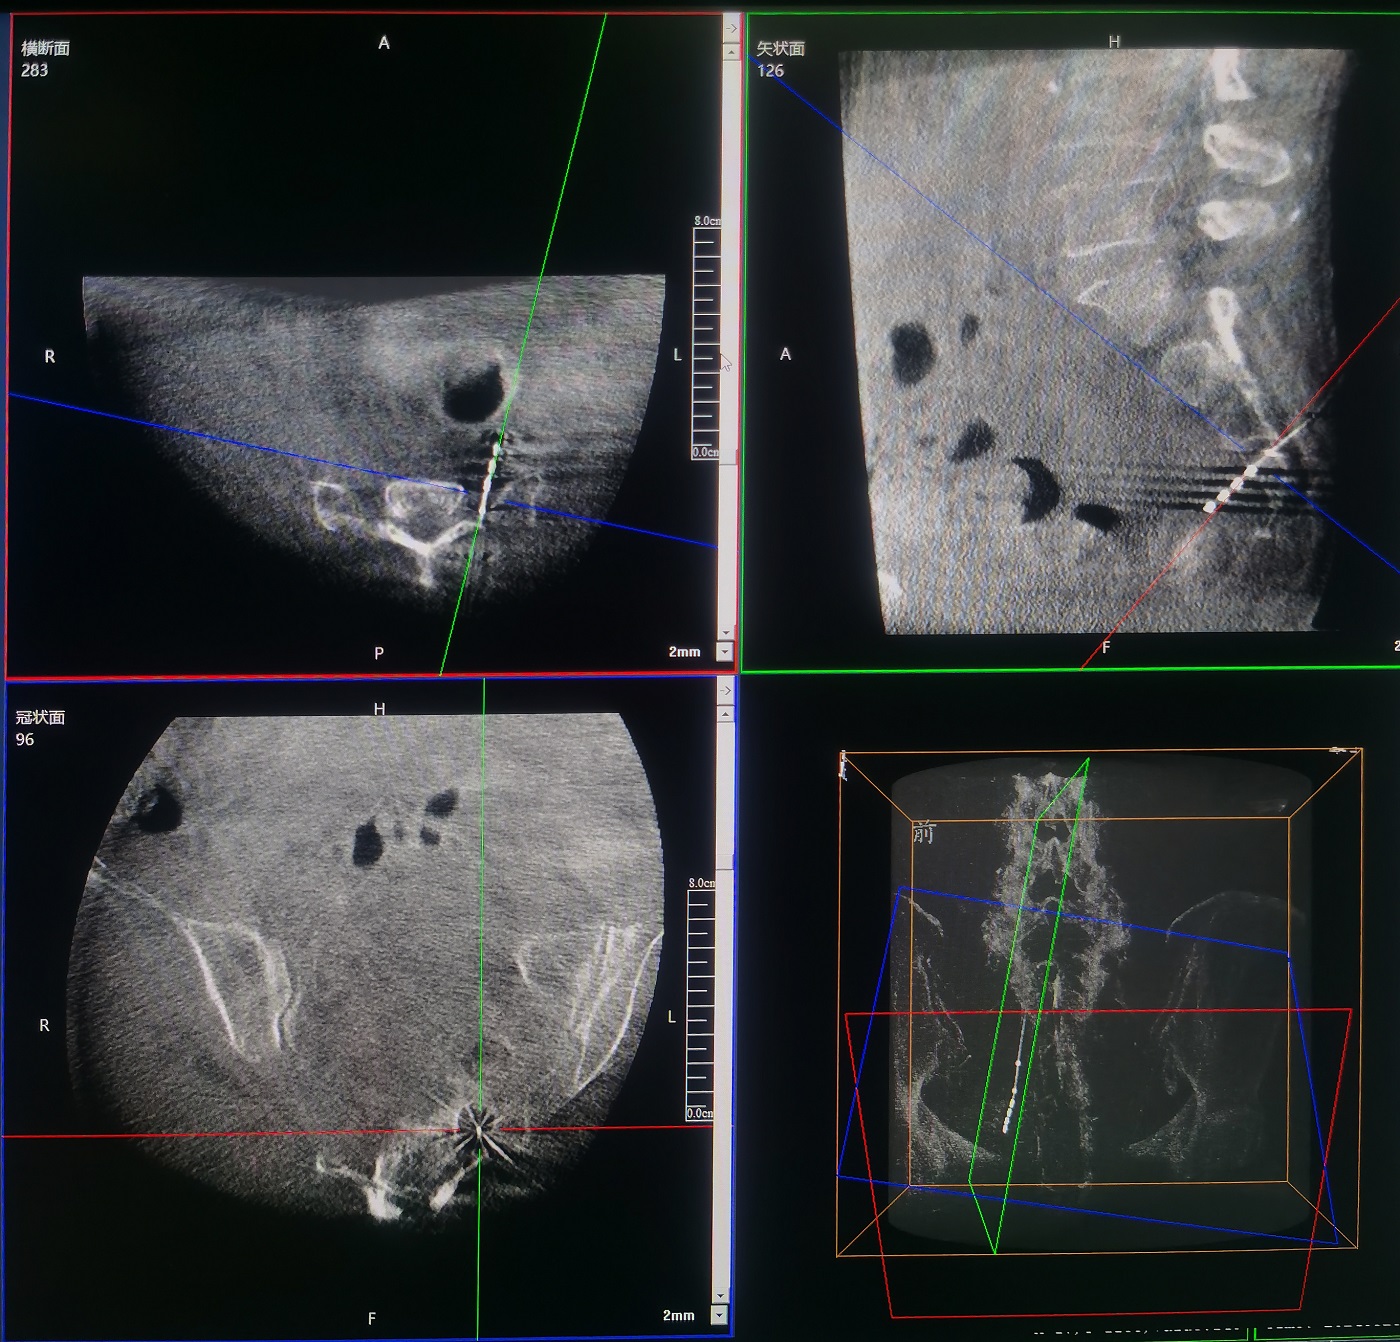

術中,運用普愛醫(yī)療三維C形臂環(huán)掃,采集骶骨區(qū)域三維圖像,在機器人導航界面上進行路徑規(guī)劃,自動引導進入骶3神經(jīng)孔。

原本需要反復透視比較和定位的骶3神經(jīng)孔,通過機器人的智能算法,一次性即可準確定位,靶向進入。

整個手術過程清晰流暢,穿刺傷口小。經(jīng)過三維C形臂透視確認,刺激器位置精準,與術前規(guī)劃位置一致。